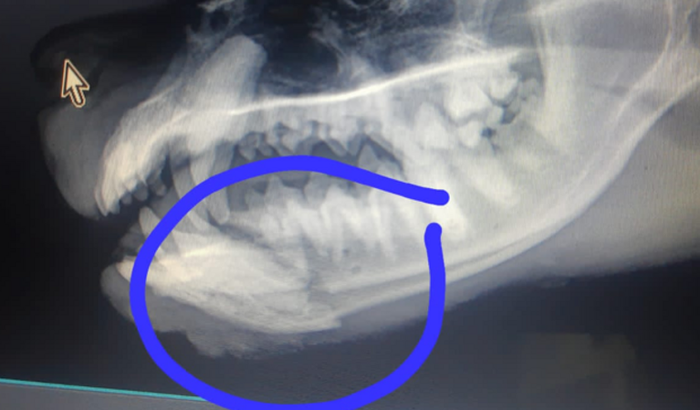

Eu está seguindo a minha rotina diária quando a minha irmã e Sobrinha me acionaram para o resgat do caramelo ( Fulgo Bebezão), ele foi atropelado e sofreu uma fratura no maxilar, onde foi esquecido por todos mas não pela a minha família. Estou Fazendo essa vakinha para arrecadar dinheiro para cirurgia dele, eu mesmo ja paguei Os valores iniciais, porém precisamos da ajuda de todos. Tudo será em total transparência e o objetivo é inicialmente continuar custeando os medicamentos e alimentos.